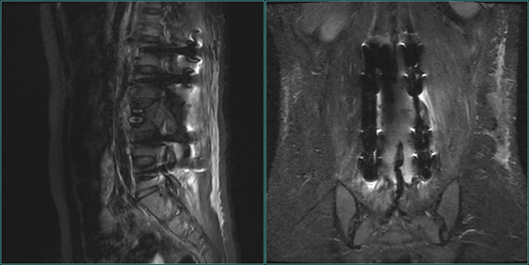

腰椎MRI显示

骨科张海龙主任对小郑进行了全面的体格检查,评估了脊柱四肢的运动、感觉和神经反射等情况,并加做了腰椎核磁共振检查。根据影像检查和其他检查结果,发现小郑是腰3椎体爆裂性骨折的骨折碎块压迫脊髓,引起双下肢的不完全性瘫痪,并且合并有马尾神经损伤。